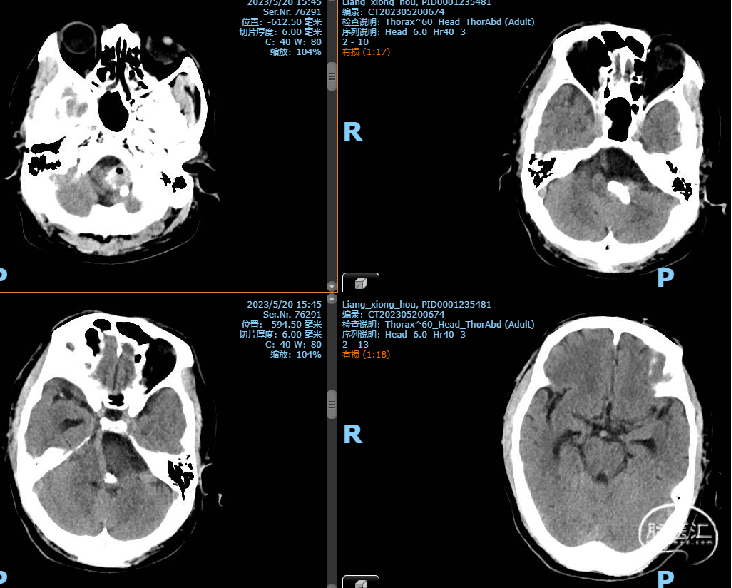

当地医院头部CT:SAH

初步诊断:1、颅内动脉瘤 2、蛛网膜下腔出血

外院首次CT影像片未带,我院复查头部CT,右侧积血较多,故优先处理右侧动脉瘤,尝试裸栓;但左侧颈眼动脉瘤形态不规则,也有可能是责任动脉瘤,拟过几日再支架辅助栓塞。

2023-05-8 手术

2023-05-10 术后CT